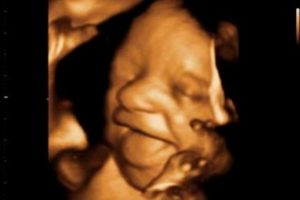

- За счет высокой четкости и полноцветности изображения повышается качество мониторинга – специалист может детально рассмотреть черты лица ребенка, мимические движения, строение позвоночника и конечностей для исключения вероятности формирования пороков и аномалий.

- Подобное знакомство с ребенком в режиме реального времени – трогательный и незабываемый момент для будущей мамы. Качество сигнала позволяет даже распознать эмоции малыша – радость, недовольство или апатию.

- Объемное изображение приближено к реальному, с его помощью можно делать даже определение черт лица младенца.

Данный формат, несет информативный характер обследования. Он помогает специалистам увидеть все процессы развития ребенка в трехмерном изображении, а так же его лицо, его мимику.